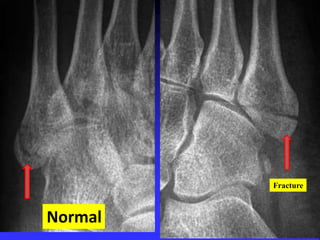

Normal

Fracture

Toddler’s Fractures

Typical nondisplaced spiral fracture of tibia

with no fibular fracture.

Initial x-ray:

often normal, diagnosis by F/U films with

lucent line or periosteal reaction

Or by ultrasound